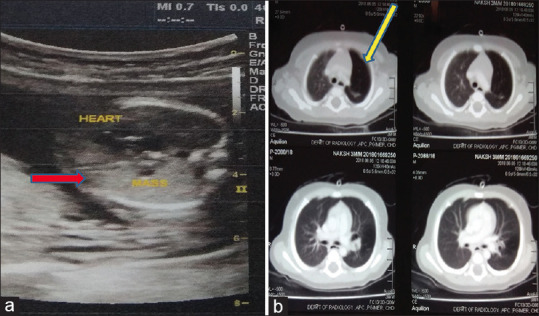

Background: Foetal thoracic lesions are uncommon, with the incidence of 1 in 15,000 live births. Antenatal monitoring of these lesions is required to prognosticate the parents about the postnatal outcome of the lesions and about the well-being of the baby. Foetal ultrasound and magnetic resonance imaging (MRI) are the modalities to detect these lesions and follow-up during pregnancy and postnatally. Congenital pulmonary adenomatoid malformations (CPAM), congenital diaphragmatic hernia (CDH) and bronchopulmonary sequestrations (BPS) are the commonly detected foetal thoracic lesions. Parameters such as congenital cystic adenomatoid malformation (CCAM) volume ratio (CVR) and lung-to-head ratio (LHR) determine the prognosis of these lesions. With this background, we planned to study the prognosis and outcome of antenatally detected thoracic lesions.

Materials and methods: This was a prospective study carried out for 2 years (January 2017 to December 2018). Pregnant females with foetuses diagnosed to have thoracic lesions on the second- and third-trimester ultrasound and foetal MRI were enrolled for the study. CVR and LHR were noted. Outcomes were analysed in terms of the need of termination of pregnancy, foetal or neonatal demise and need of surgery or conservative management.

Results: Of a total of 521 pregnancies, thoracic lesions were detected in 22 (4.22%) cases. Individually, the incidence of each lesion was: CPAM-10 (45.45%), BPS-5 (22.73%), CDH-5 (22.73%) and congenital higher airway obstruction-2 (9.1%). Chromosomal screening was normal in 100% of cases. Follow-up was done for 2 years. Termination of pregnancy was required in 3 (13.64%) cases, postnatal death occurred in 4 (18.2%) cases, surgery was required in three cases of CDH soon after birth and two cases of extralobar BPS at 2 years of age. 10 (45.45%) cases were managed conservatively, who are doing well at 2-year follow-up.

Conclusion: CPAMs, BPSs and CDH are the commonly detected antenatal thoracic lesions. Ultrasonography and MRI help detect and prognosticate the parents about the outcomes of these lesions. CVR and LHR with associated congenital malformations are important prognostic markers for these lesions. There is a need of long-term prospective studies to delineate the natural history of these lesions.